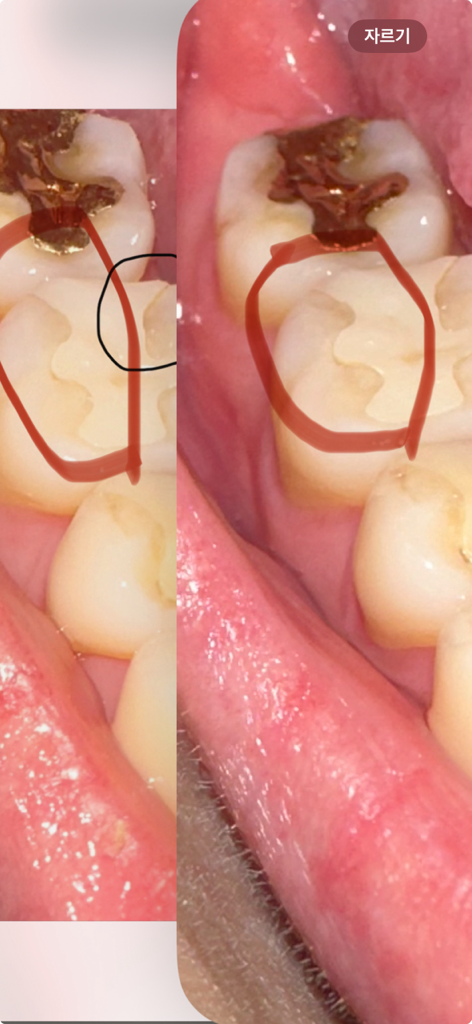

치과에서 이빨을 다듬어주셨는데 원장님이 잘못 이해하고 다른곳 멀쩡한 부분을 다듬어주셨습니다.. 그래서 더 파여보입니다 ㅠㅠ 혹시나 치아가 더 빨리 닳게되거나 다른 문제가 생길수도 있을까요? 오른쪽이 치료 후 입니다 제발 답변 부탁드립니다 ㅜㅜ

• 1번 째 사진